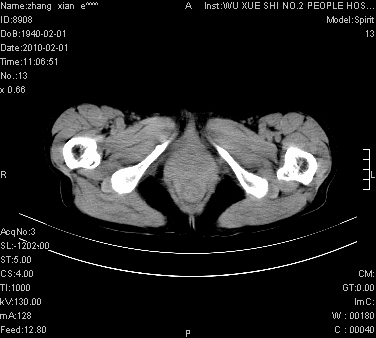

标题: CT24434:70岁 女 腹胀,腹水原因待查 [打印本页]

标题: CT24434:70岁 女 腹胀,腹水原因待查

大量腹水,脾脏囊性占位,子宫颈占位,右侧腹股沟淋巴结肿大,建议+c,先查妇科。

腹盆腔大量积液,子宫增大,子宫颈增大外形不规则,内见低密度影,膀胱后壁显示不清,右腹股沟肿大淋巴结,脾脏囊性占位,子宫颈占位,子宫颈癌?建议增强。